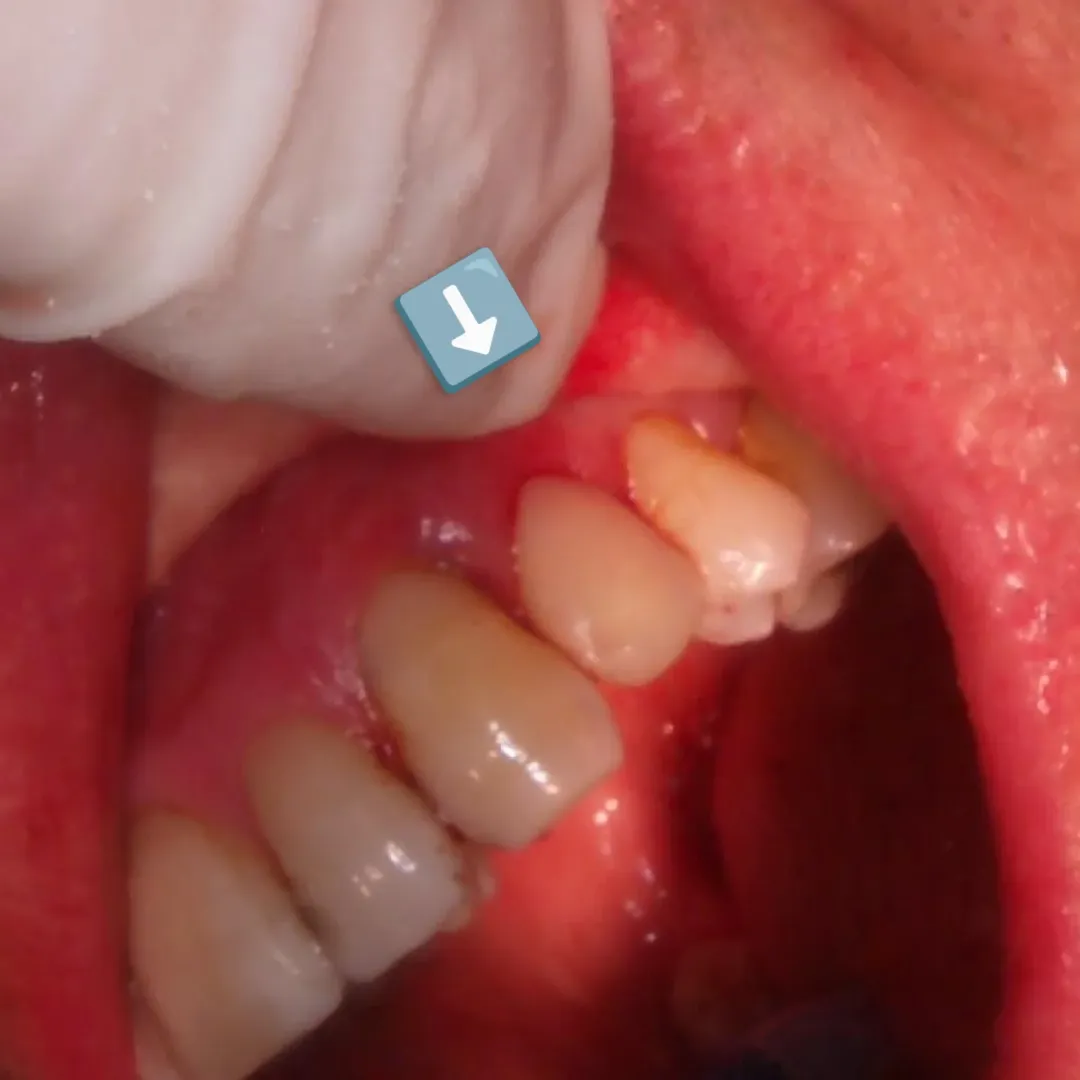

- Carga imediata com provisório aparafusado: Obtivemos o torque necessário para avançar com a instalação de um provisório aparafusado imediatamente após a cirurgia, diretamente em consultório.

O provisório imediato funciona como um condicionador de tecidos, mantendo o perfil de emergência e preservando as papilas interdentárias que seriam perdidas num processo de cicatrização convencional sem dente.

Nas imagens, é possível acompanhar a sequência completa: desde as radiografias iniciais com o dente comprometido, passando pela fase cirúrgica com a extração e colocação do implante, até ao provisório aparafusado em posição. A radiografia final confirma o bom posicionamento do implante e o preenchimento adequado do gap vestibular.